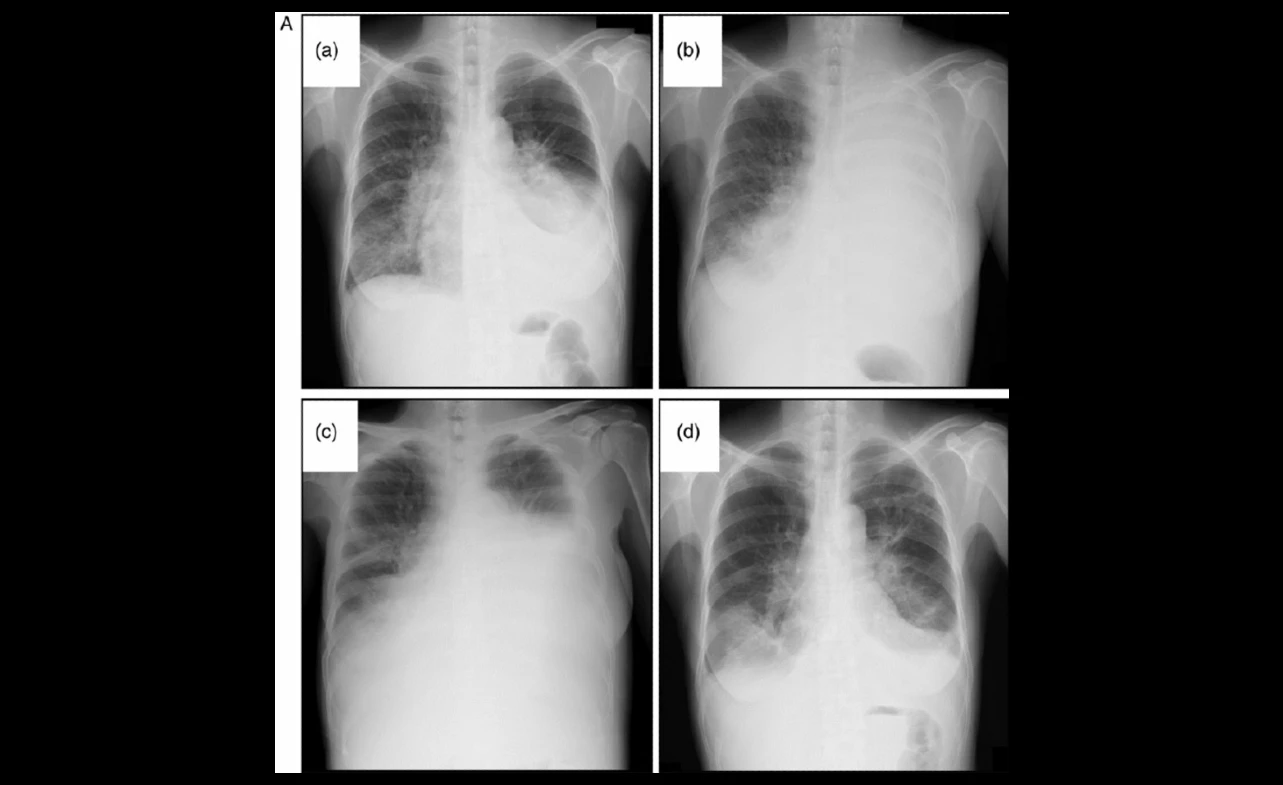

The journey to improving outcomes in non-small cell lung cancer (NSCLC) therapy has been marked by the advent of targeted treatments such as crizotinib. As clinical results have accumulated, the treatment effectiveness of crizotinib has become crystal clear. This targeted therapy, initially approved based on its molecular mechanism of action, now boasts compelling evidence from various clinical studies that emphasize not just its efficacy but also its potential in enhancing patients’ quality of life.

Clinical trto enhancel in assessing crizotinib clinical results reveal noteworthy findings. In several of these studies, crizotinib demonstrated significant improvement in tumor response rates compared to traditional chemotherapies, establishing it as a formidable opponent in the battle against lung cancer harboring ALK or ROS1 genetic alterations.

In real-world scenarios, crizotinib continues to mirror the effectiveness recorded in controlled studies. The introduction of crizotinib into the therapeutic regimen of NSCLC has shifted the paradigm, offering patients a potent option that more precisely targets their cancer’s unique genetic makeup. Evaluating the NSCLC therapy landscape, crizotinib’s role becomes indispensable, as it provides a non-invasive treatment alternative with a lower burden of side effects and a demonstrable improvement in the quality of life for patients with advanced lung cancer.